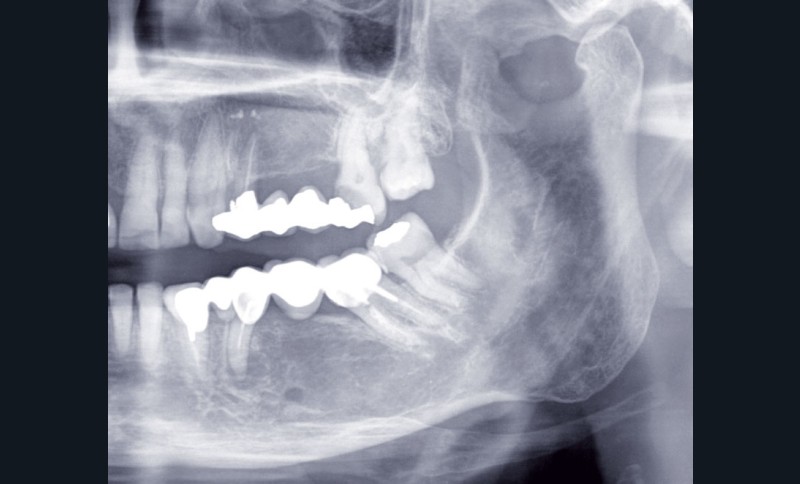

Après dépose du bridge mandibulaire et reprise du traitement endodontique, un bridge transitoire est réalisé à partir du wax-up. Une empreinte de celui-ci est faite avec Imprint™ 4 Preliminary Penta™ (3M ESPE).